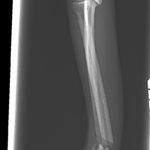

橈骨固定術 #249 Toy Poodleさんがソファーからジャンプして橈骨骨折をしたとのことで主治医の先生から固定術の依頼がありました。1.5 Titanium Locking Plateで固定術を行いました。しばらくは安静が必要です。 症例カテゴリー 放射線治療整形外科軟部組織外科脳神経外科内科腫瘍外科救急・集中治療リハビリテーション科腫瘍内科内視鏡科脳神経科呼吸器外科中医・漢方猫の腎移植循環器科